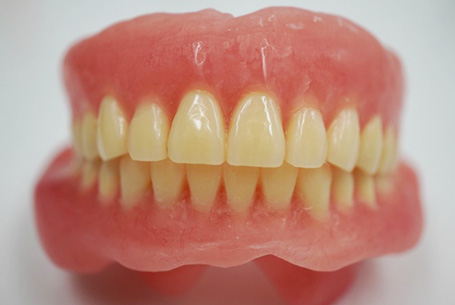

こちらの患者さんは上下総入れ歯を使用中でした。

下の入れ歯は吸着がなく、すぐに外れる状態でした。入れ歯辺縁の長さが長く、頬小帯部も強く押し込んでいたため、口を動かすたびに筋肉により入れ歯が持ち上がっていました。

また、バランスの良い噛み合わせではなかったため、入れ歯ががたつき、噛みにくい状態でした。

歯並びの位置の変更が必要であったため、新しく入れ歯を製作することにしました。

治療前にご使用中の上下総入れ歯